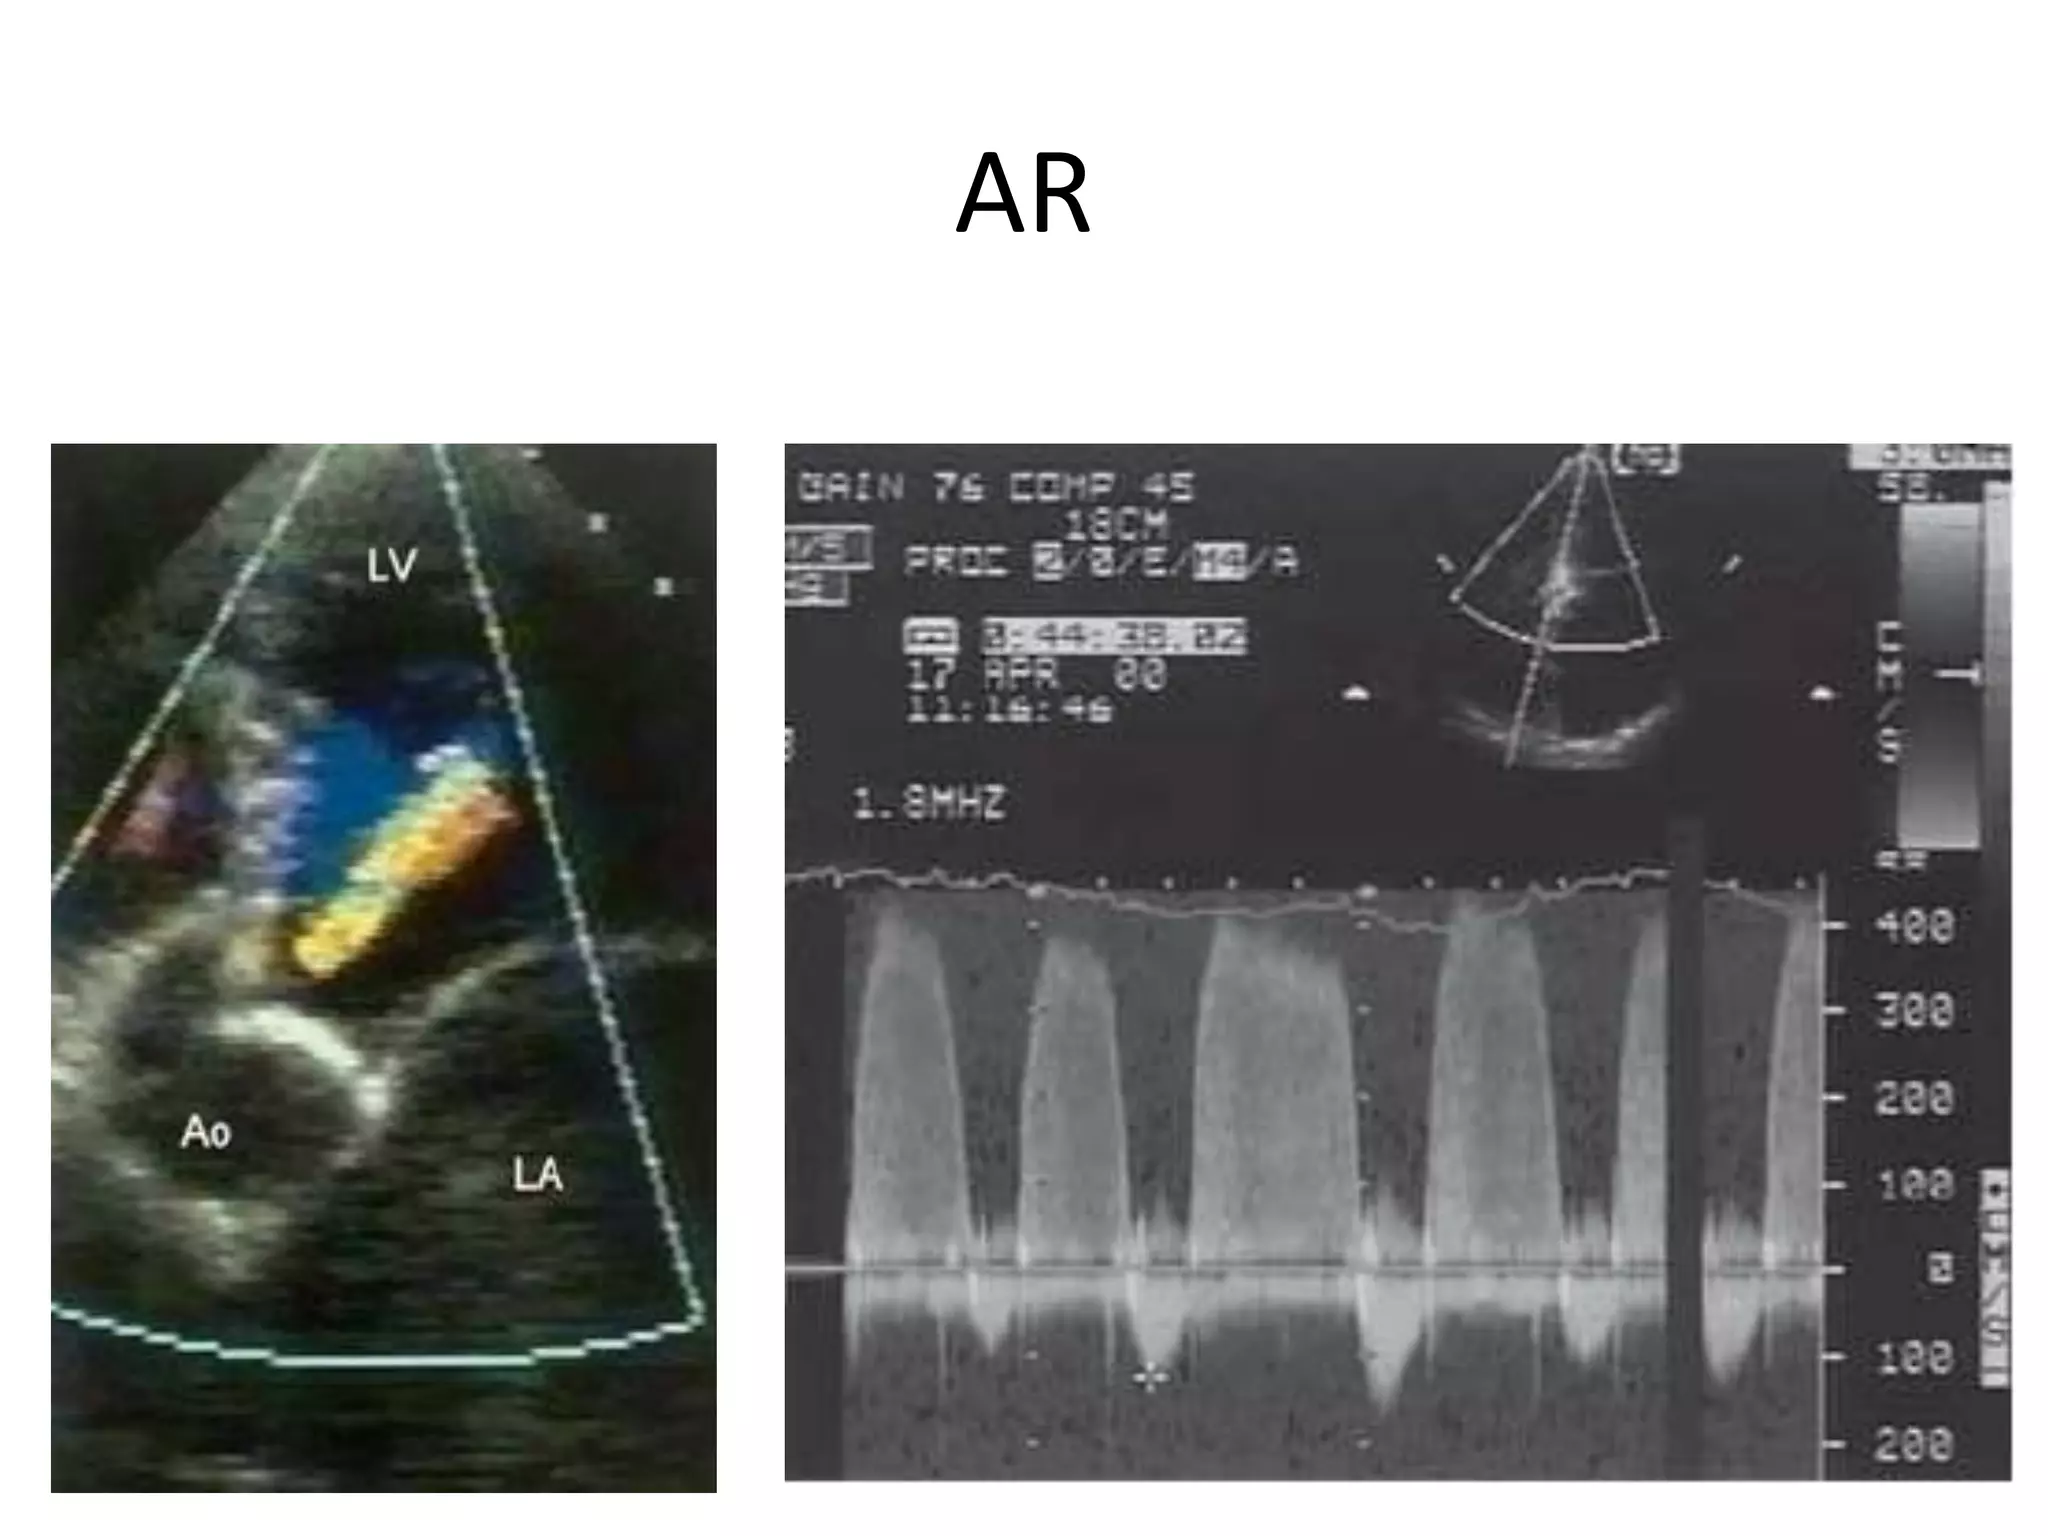

AR